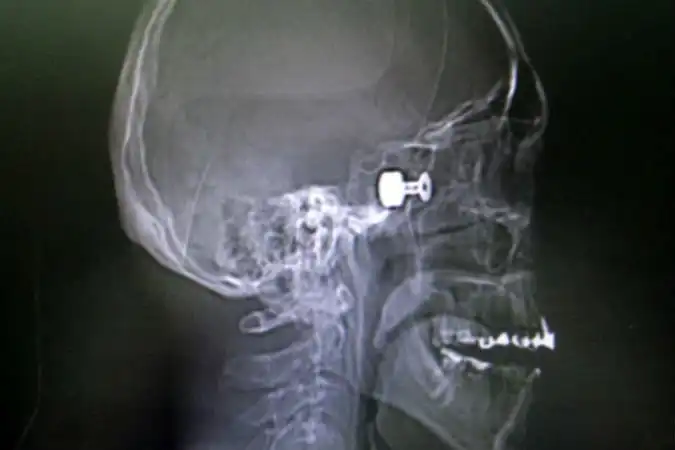

Про пациента Краевой клинической больницы, которого привезли накануне с пулей в голове (в прямом смысле слова), можно смело говорить – заново родился. Сам-то он ничего не помнит, только момент выстрела из травматического оружия. И прямо в глаз…Мужчина может считать этот день вторым рождением.

Сначала раненного доставили в глазной центр, где врачи удалили глазное яблоко. Потом перевели в краевую больницу. Отолорингологи краевой больницы провели, по сути, уникальную операцию высокотехнологичную операцию, чтобы извлечь из головы пациента пулю размером с орех. Самое опасное, что она находилась прямо в миллиметре от мозга молодого мужчины.

- Инородный предмет врачи ювелирно удалили под микроскопом, с применением эндоскопа через носовое отверстие, — рассказали в пресс-службе Краевой клинической больницы. — В настоящее время состояние пациента не вызывает у врачей опасений за его жизнь.